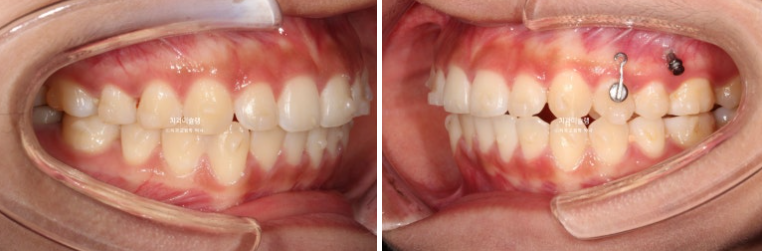

24년 여름방학을 이용해서 교정상담을 온 유학생 환자분입니다.

측절치의 개방교합, 아래 앞니 덧니 등 보입니다.

우측 교합관계는 1급에 가깝지만

좌측 교합관계는 2급입니다.

위 아래 치아들이 일대일로 물리면 2급 또는 3급 교합관계 입니다.

송곳니에서 큰어금니까지 절반씩 엇갈려 물리는 교합이 1급 교합입니다.

사랑니를 빼고 사랑니 공간으로 어금니를 후방이동 시켜 교합관계를 맞추고 덧니 해소할 공간을 얻기로 합니다.

돌출이나 뻗침은 없어서 비발치로 진행하는 것 입니다.

인비절라인 컴프레헨시브 프로그램으로 교정치료에 들어갔습니다.